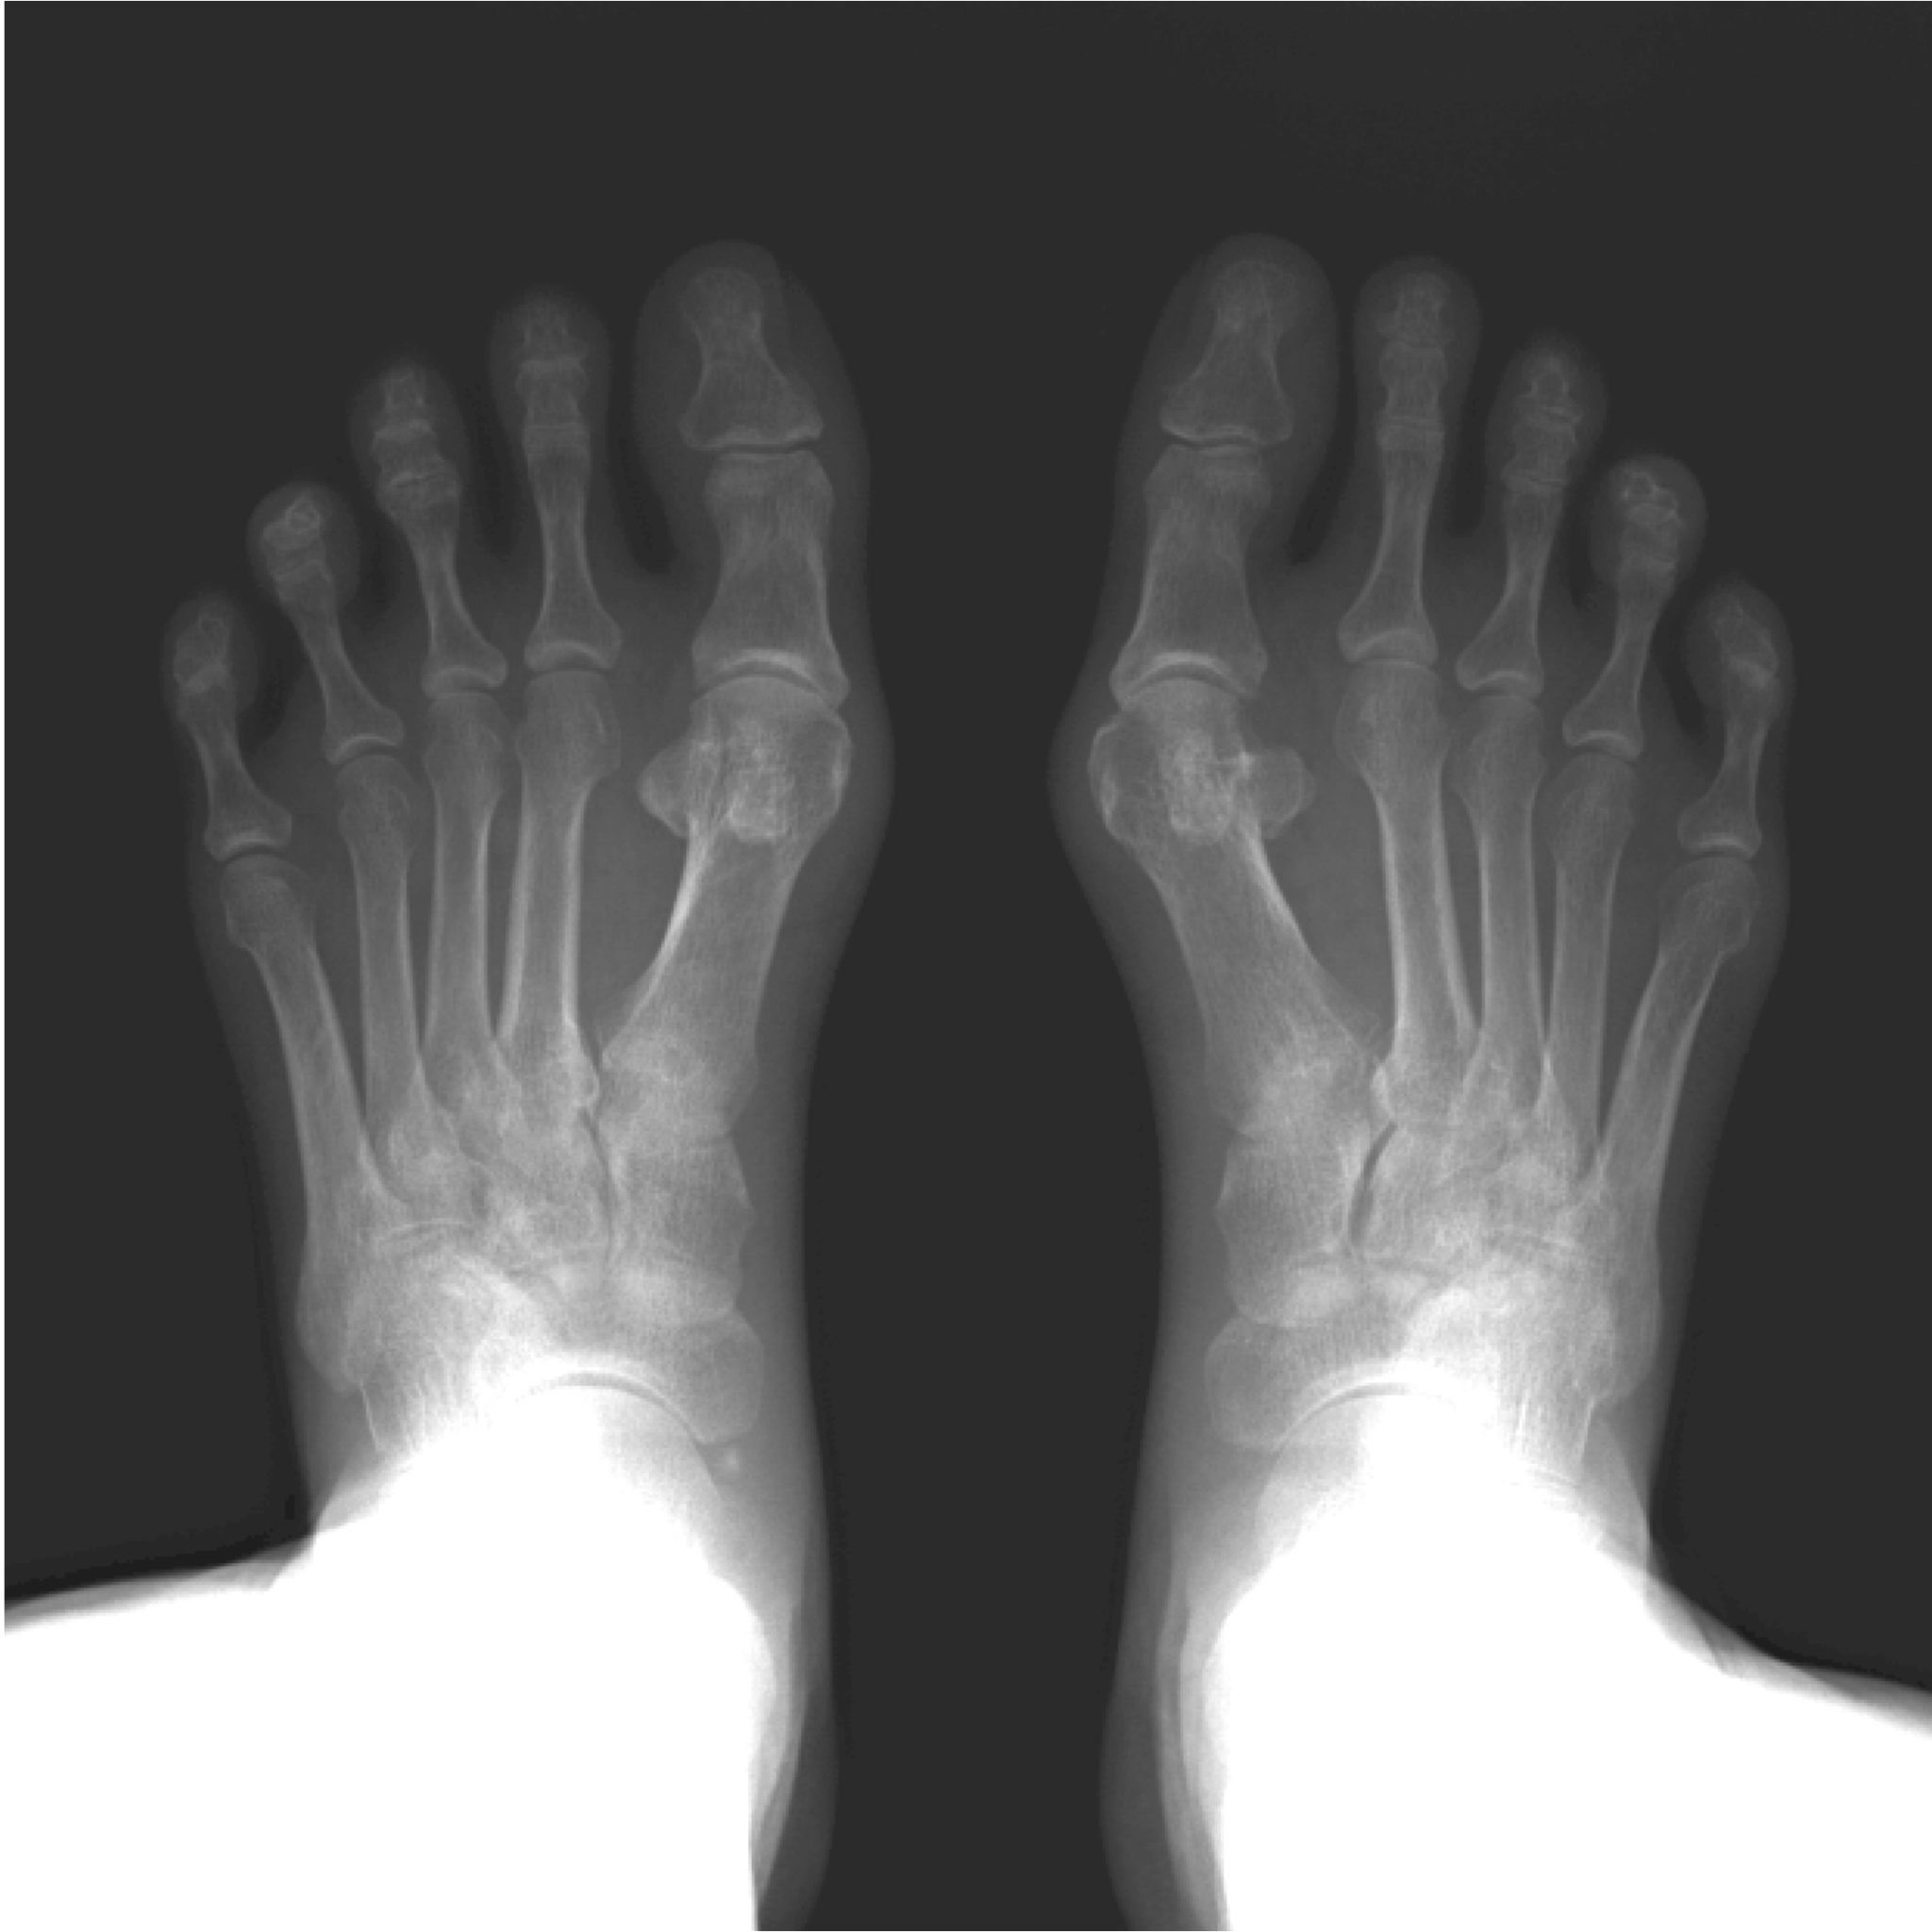

外反母趾の角度が大きいほど、前後方向の姿勢揺れが増える傾向

40歳以上の169名を対象にした調査では、

- 外反母趾の角度が大きい → 前後方向の姿勢揺れが大きい傾向

- 下肢筋量が少ない人ほど揺れが大きい

という結果が報告されています。

外反母趾のような“足指の変形”も、

姿勢制御に影響する可能性があることを示唆しています。